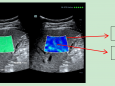

在慢性肝病的诊断与监测中,一种名为剪切波弹性成像(ShearWaveElastography,SWE)的技术正发挥着关键作用。它凭借无创、精准的优势,成为评估肝纤维化程度的重要临床工具,为医生制定治疗方案、追踪病情变化提供了有力支持。今天,我们就来深入了解这位肝脏健康的“侦察兵”。肝纤维化是慢性肝病发展的关键阶段,若不及时干预,可能进一步发展为肝硬化甚...